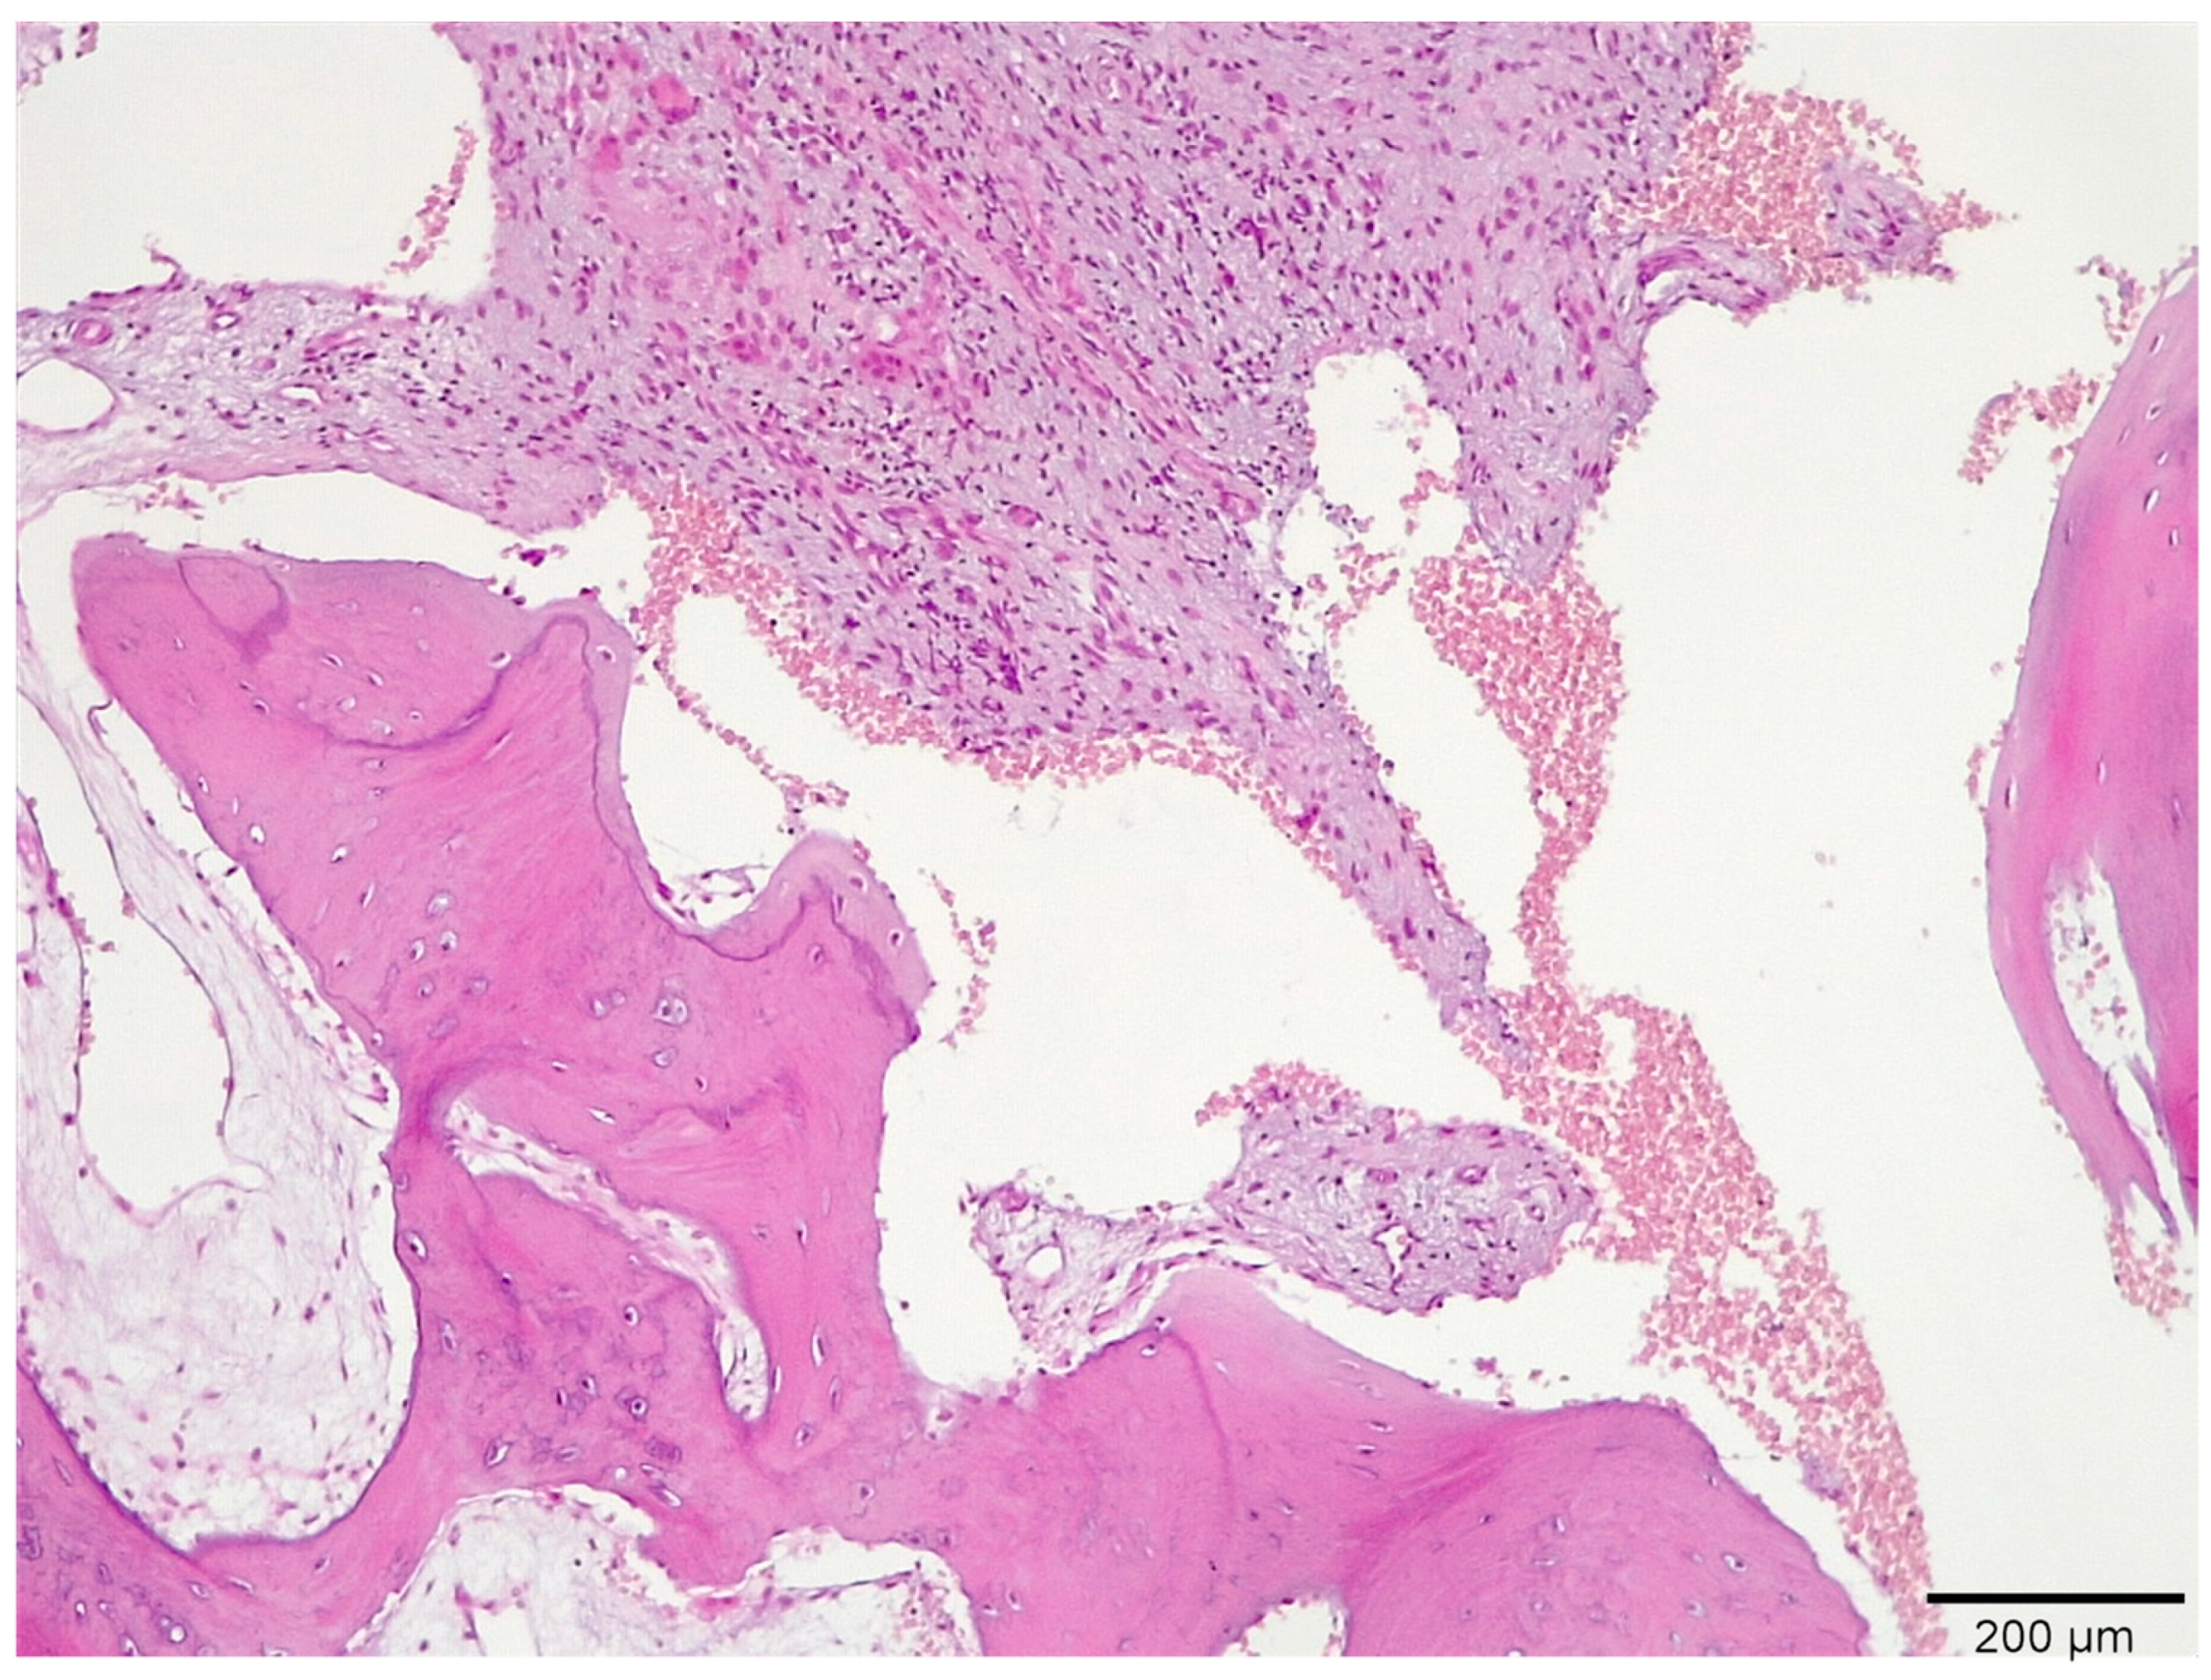

3.1. Histological Analysis Showed Signs of New Bone Formation at 60 Days

3.2. Histologic Data Obtained after Samples Analysis at 24 Months of Evaluation

| New bone | 16.3 ± 1.98 | 41.1 ± 0.76 | 54.5 ± 0.24 | 59.4 ± 1.23 * |

| Residual Graft | 37.1 ± 0.34 | 30.0 ± 0.45 | 21.3 ± 0.88 | 15.6 ± 086 |

| Connective tissue | 46.6 ± 0.11 | 29.9 ± 0.56 | 24.2 ± 0.32 | 25.0 ± 0.44 |